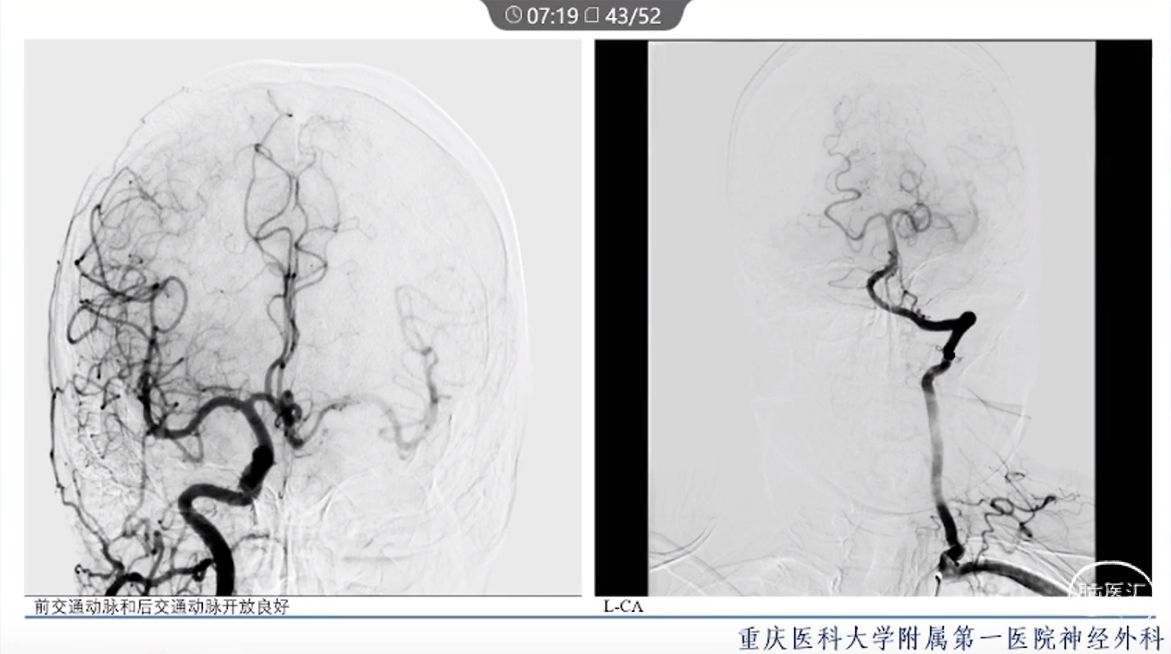

·颈内动脉颈段动脉瘤治疗方式有血管内治疗、外科手术和保守治疗。

·血管内治疗是最常见的治疗方式,随着血管内介入技术的发展和材料的进步,越来越多的动脉瘤可以通过血管内途径治疗。

·对于血管扭曲、血管直径大以及存在抗血小板禁忌的动脉瘤患者,特别是对于颈段大型或巨大型动脉瘤的治疗,常需要外科手术治疗。